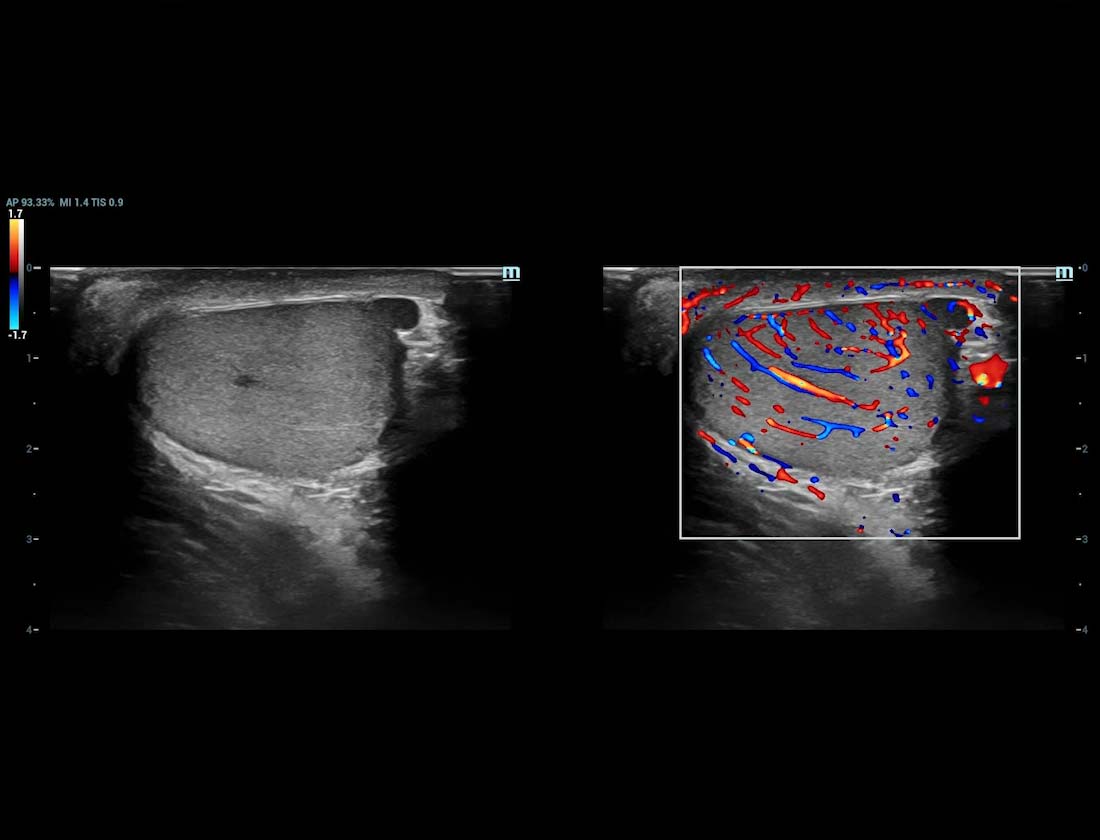

Ultra Micro Angiography (UMA)

UMA migliora la sicurezza diagnostica ampliando la visibilitĂ dei flussi sanguigni fino al livello dei vasi piĂč piccoli, con una sensibilitĂ e una risoluzione superiori.

Rene sUMA

Massa mammaria cUMA

Massa mammaria

Testicolo UMA

Rene PUMA